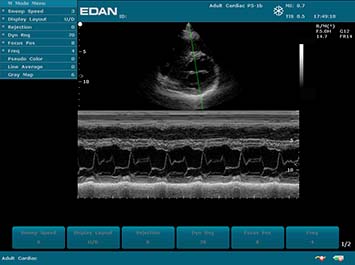

Клинические изображения